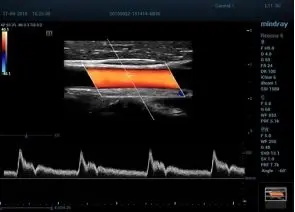

HR-flow™ режим отображения кровотока с высоким временным и пространственным разрешением для точной и однородной визуализации сосудов, в том числе самых мелких

Smart Doppler интеллектуальная оптимизация доплеровских режимов

Smart Track автоматическая подстройка расположения и угла наклона рамки цветового допплера с автоматическим отслеживанием положения контрольного объема